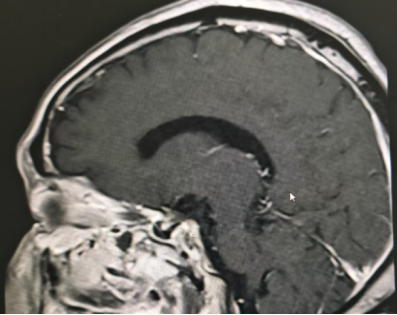

患者为69岁男性,因持续性头痛、视力下降伴双眼颞侧视野缺损前往阆中市人民医院神经外科就诊。经综合评估,结合内分泌检查及1.5T MRI动态增强扫描,确诊为垂体大腺瘤(2.0cm×1.7cm×1.7cm),肿瘤向上压迫视交叉,并伴有蝶窦气化不良。

针对该病例,垂体瘤多学科诊疗中心(MDT)多次组织讨论。鉴于传统开颅手术创伤大、恢复周期长,团队最终决定采用经鼻蝶内镜垂体瘤切除术。该微创技术通过鼻腔自然通道进入蝶鞍区切除肿瘤,具有创伤小、出血少、恢复快等优势。

手术过程中,团队在神经导航精准定位下,经鼻腔自然通道建立微创手术入路,完整切除肿瘤的同时最大限度保护正常组织结构,手术切口仅约2.0×1.5cm。术后患者恢复良好,无并发症发生,症状明显改善,目前已康复出院。